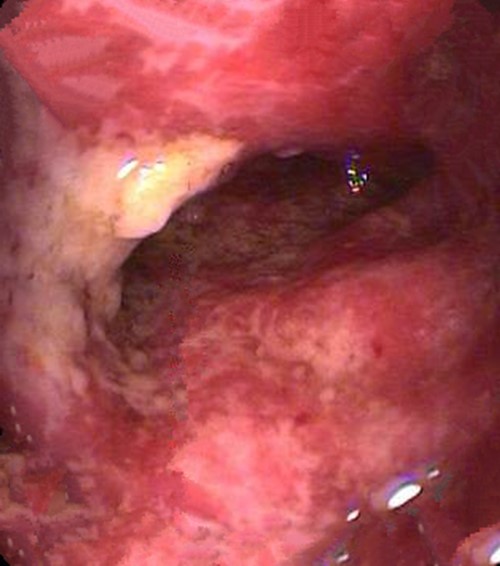

嚴重慢性結腸炎腐爛的

缺血慢性結腸炎患者

缺血性慢性結腸炎的

缺血性慢性結腸炎患者